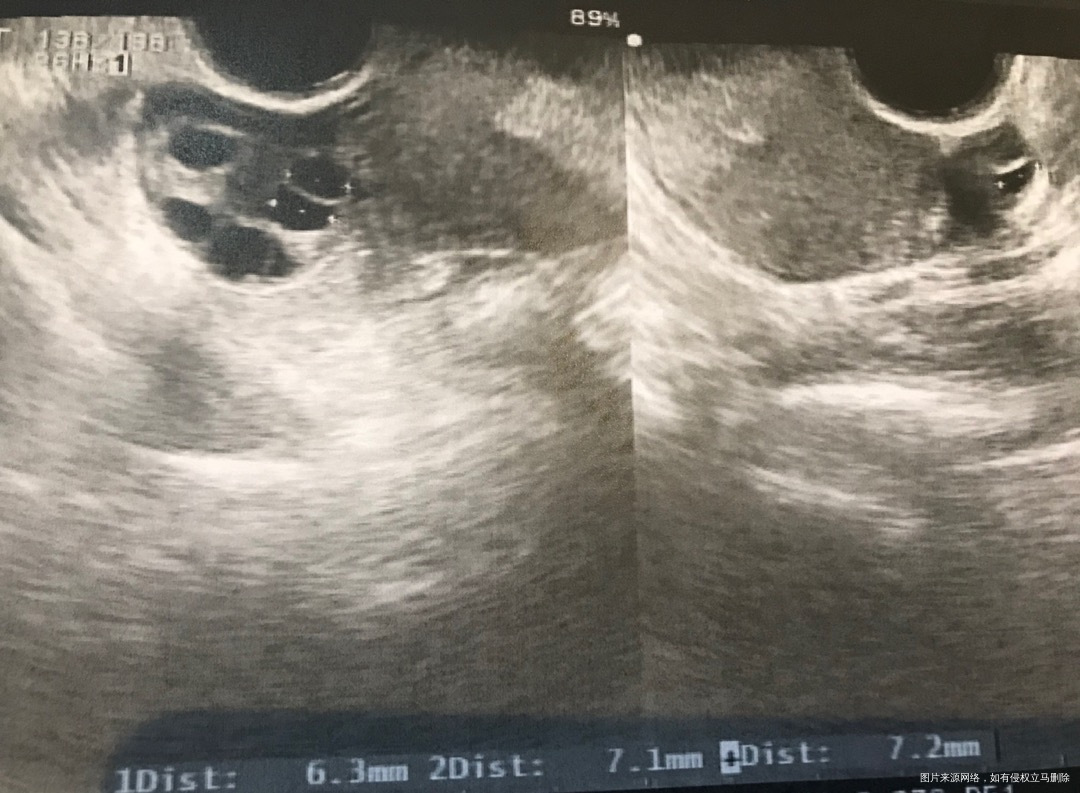

月经第四天查窦卵泡数,请看看图是否正常?左侧只有1个,右侧5个正常吗?监测排卵半年只有右侧排卵,左侧子宫和卵巢间有粘连,左侧卵巢什么问题导致不排卵?另外说我窦卵泡数比前几个月多了,这是好还是不好?

您好,每个月的窦卵数都会不太一样,你目前的窦卵数还是比较少的,提示卵巢功能储备不足,可以结合基础性激素和AMH评估下。左侧可能功能比较不好,窦卵少没有卵泡发育,加上粘连也可能影响排卵。建议您这种情况还想生育的话可以考虑试管助孕。

匿名用户 回复 王小婷:我的amh是3.0,月经期FSH是4.9。综合来看是卵巢功能低下吗?

匿名用户 回复 王小婷:雌激素14,LH4.7

王小婷 回复 匿名用户:这个卵巢功能还不错的。对了,这个窦卵不是只看这个切面数的,要综合看。输卵管检查过吗?